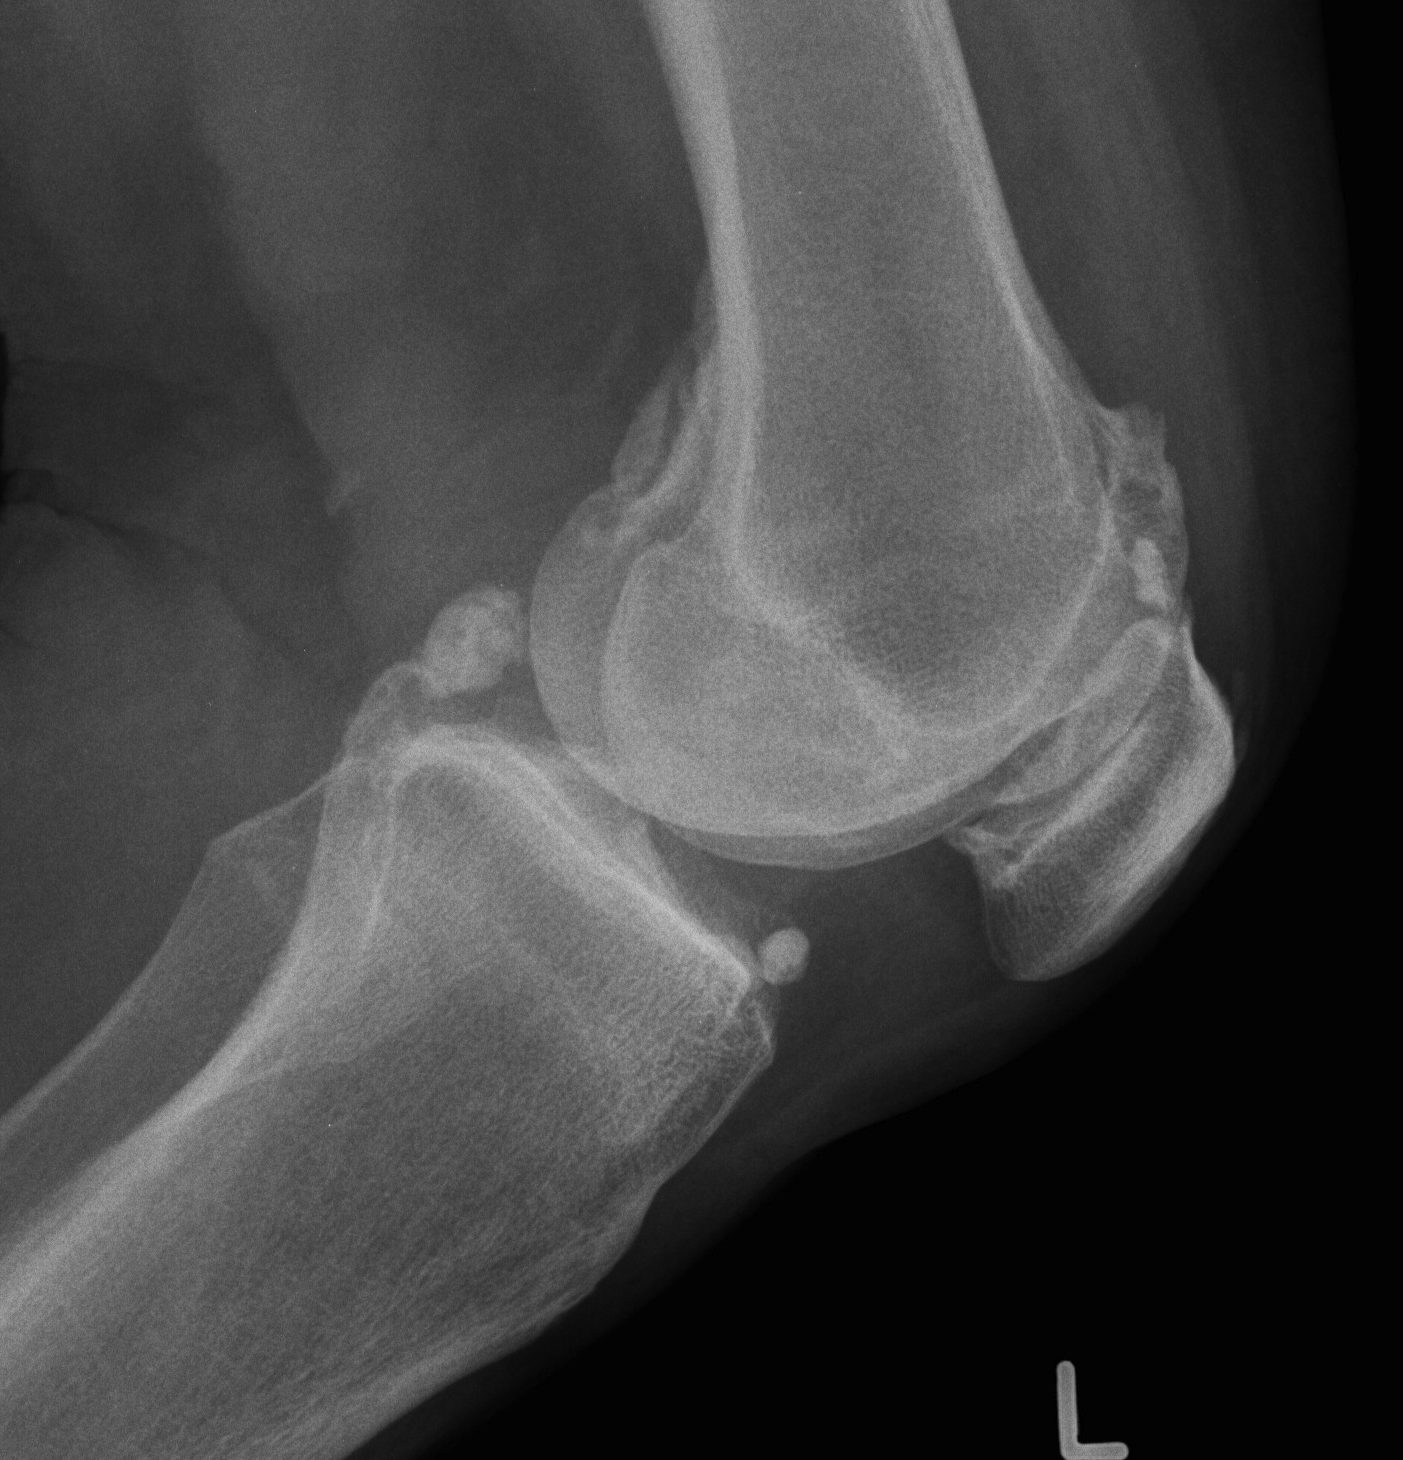

Xray

OA Loose Bodies

OCD Loose Bodies